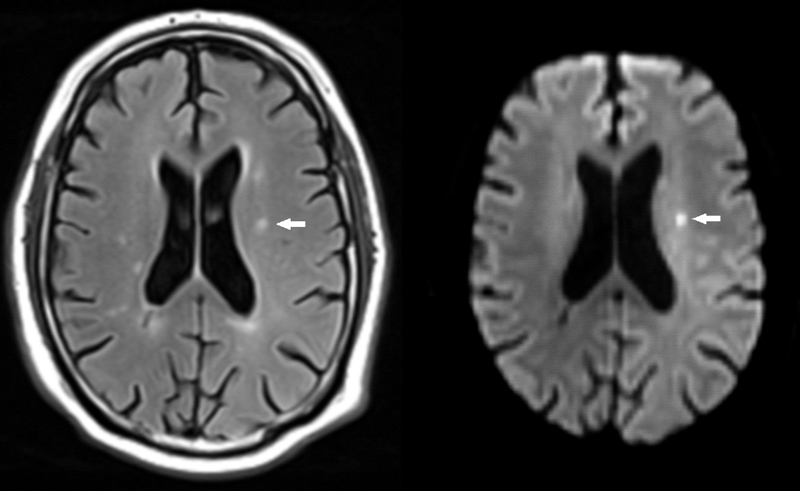

Cerebral magnetic resonance imaging (cMRI) provides detailed information on brain structure and function. The occurrence of silent cerebral infarctions (SCI), which have been found in up to 11% of individuals from the general population [13], could be mechanistically involved in the occurrence of cognitive impairment among AF patients (fig. 1). Cerebral microbleeds (fig. 2) are another structural correlate that potentially explain the link between AF and cognitive dysfunction [14], as some studies found a higher prevalence of microbleeds in patients with stroke or transient ischaemic attack (TIA) and a history of AF [15]. Other factors such as progression of the arrhythmia, concomitant diseases or medical treatments may also contribute to the cognitive decline in AF patients.

Figure 1 Small ischaemic stroke.

A small subacute ischaemic stroke is depicted on fluid attenuated inversion recovery (FLAIR, left, arrow). The lesion shows signs of restricted diffusion and is hyperintense on diffusion weighted imaging (DWI, right, arrow)